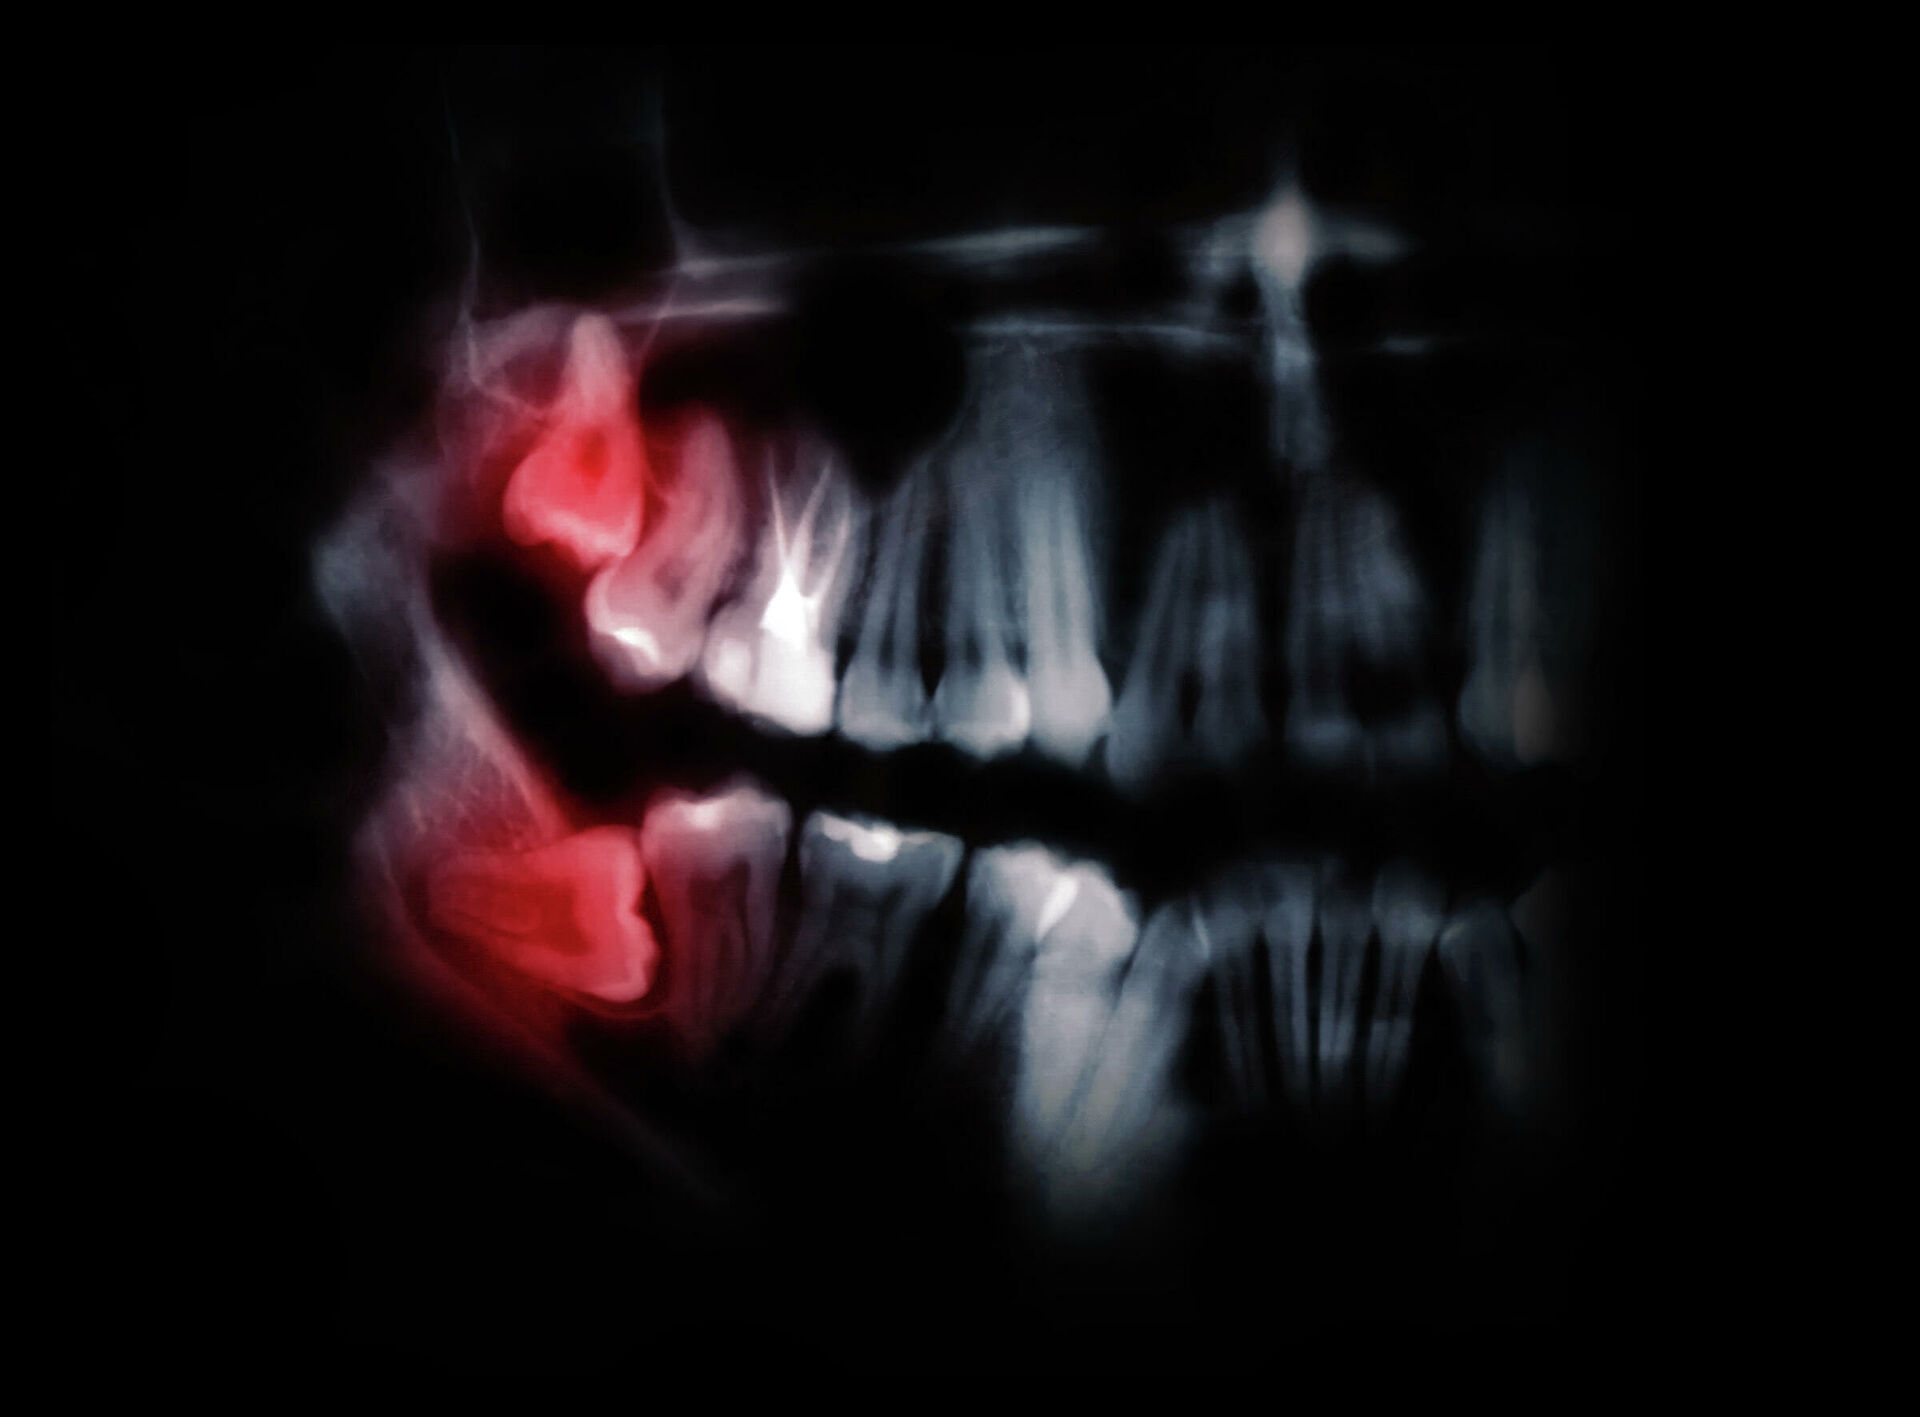

Еще один важный признак продолжающейся эволюции — отсутствие зубов мудрости почти у 20 процентов европейцев. Все чаще специалисты не наблюдают у пациентов даже зачатков этих моляров. А если они и есть, то занимают неправильное положение или не прорезываются до конца. Это вписывается в общий эволюционный тренд и связано, скорее всего, с изменением рациона, отмечают американские, австралийские и скандинавские исследователи.

У 20 процентов европейцев зубы мудрости отсутствуют. А их обладатели часто сталкиваются с тем, что они либо занимают неправильное положение (как на рисунке), либо не прорезываются до концаЭтот тезис ученые из Гарвардского университета (США) подтвердили экспериментально. Набрали несколько десятков взрослых добровольцев и разделили на группы. Одни ели мясо, вторые — батат, третьи — морковь и свеклу. Продукты либо не обрабатывали вообще, либо крайне незначительно. Ученые измеряли, сколько сил прикладывали испытуемые, чтобы прожевать разные продукты.Авторы работы подсчитали: переход с корнеплодов на мясную диету сократил время жевания на 17 процентов, плюс усилий нужно на 26 процентов меньше. Поэтому размеры челюсти и зубов у древних людей сократились. В будущем, по мнению ученых, задние моляры могут вообще исчезнуть за ненадобностью.